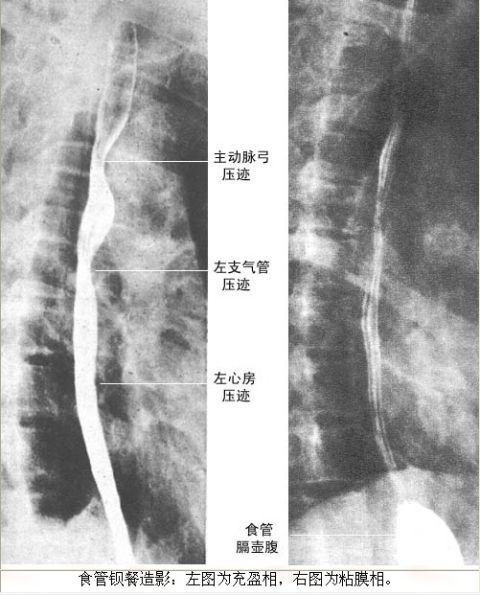

与胃镜相比,X线胃肠透视(X线消化道钡餐)检查的特点是:临床上应用历史更久,一般人认为检查时痛苦小,价格相对亲民。可以从整体上了解病变的部位,大小和与整个胃的关系,整体上可看清胃的形态,蠕动状态,病变部位较胃镜准确。